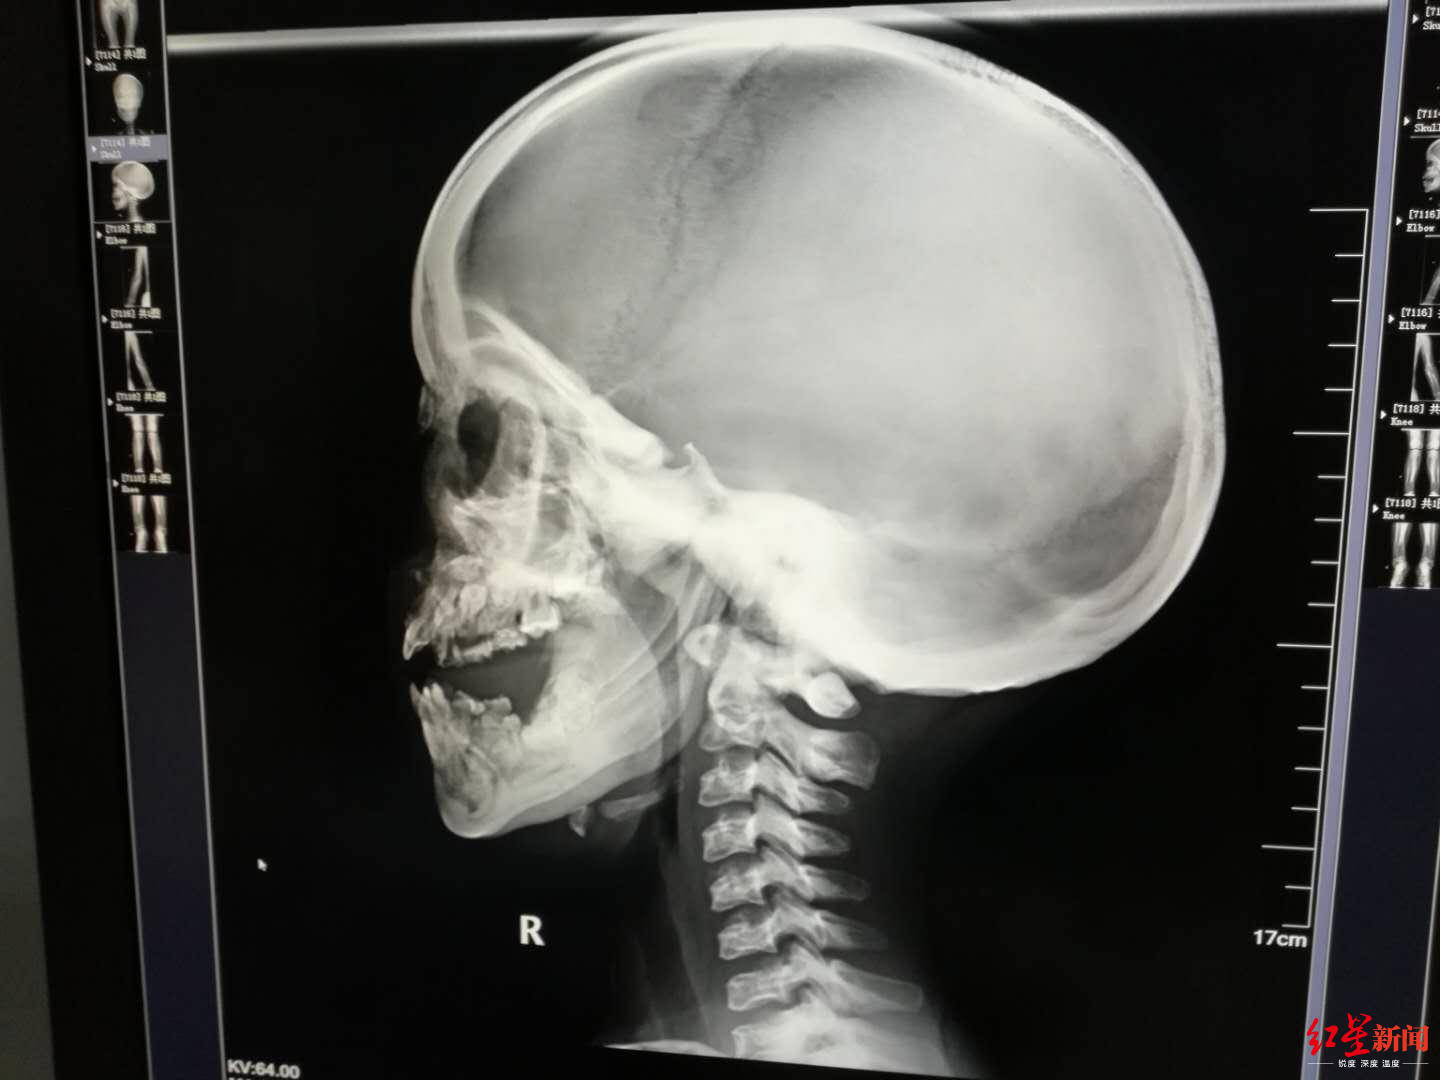

↑小女孩最终被确诊为患有石骨症,患者接受了DR检查。受访者供图

此时已经是7月1日,玄玄住进耳鼻咽喉头颈外科20多天,徐幼马上给玄玄安排了全身DR骨扫描检查,第二天出结果,徐幼第一时间到放射科看片子,结果让她大吃一惊,又反复去看了多次,脑海里蹦出一个词:石骨症。

原来,从片子上看,玄玄从头骨到四肢、到脊椎,全身的骨头都发生的变化,骨质密度增高,骨髓腔闭塞,“正常人,骨髓腔里都是红色的骨髓,有造血的功能,但她的骨头,已经石化改变。”徐幼说,简单地理解,玄玄的骨头,从中空的变成了实心的,像大理石一样。